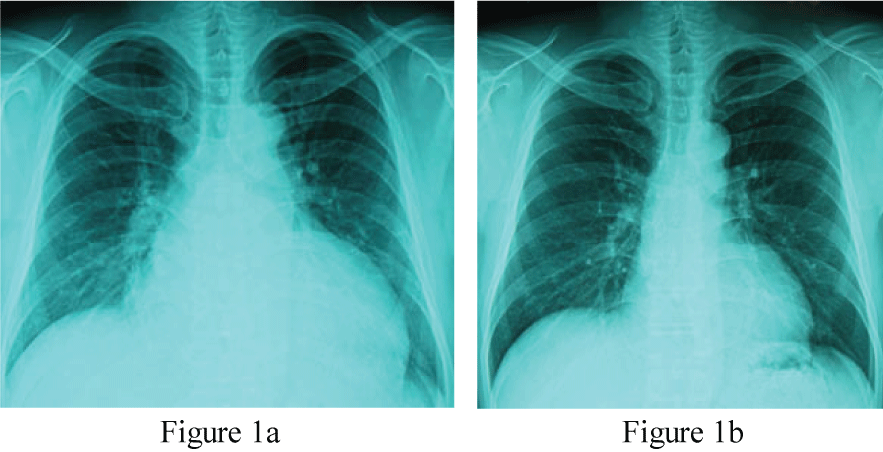

On examination, he was orthopnea condition. The temperature was 36.4 centigrade, and the pulse rate 104 beats per minute, regular, the blood pressure 170/100 mmHg, and the respiratory rate 25 per minute. The body height 179 cm, the body weight 102.2 kg, and the body mass index 31.9 kg/m2. Pulmonary course crackle was audible bilaterally, and the third heart sound gallop was manifest. The chest X-ray film taken after the emergency room treatment (Figure 1a) showed cardiothoracic ratio (CTR) 65% and the interstitial edema pattern. Electrocardiogram was regular sinus tachycardia with T wave inversion at leads I, aVL, V5 and V6, consistent with left ventricular hypertrophy.

Figure 1: Chest X-ray taken immediately after the emergency room care (Figure 1a, CTR 65%) and that taken 6 months after the therapy (Figure 1b, CTR 47%).

CTR: cardio thoracic ratio (%).

Clinical course and therapeutic interventions for the treatment of acute heart failure due to hypertensive heart disease and chronic kidney disease stage III (BUN 37.2 mg/ml and creatinine 1.79 mg/ml) were displayed in Figure 3. The acute phase treatments according to the guideline-based standard medical therapy using furosemide, alfa-natriuretic peptide (carperitide), vasodilators (eplerenone and long-acting nifedipine), and beta-blocker (carvedilol) brought good blood pressure control and improved congestive conditions. Because of the obesity and elevated blood pressure, presence of OSA was suspected initially, but the type-3 polygraphy revealed complication of CSA rather than OSA (Table 1). Thus ASV during night was induced. We used the ASV (AutoSet™ CS, ResMed, Sydney, Australia) in terms of the default settings (PEEP 5 cm H2O, minimum pressure support 3-5 cm H2O, maximum pressure support 8-12 cm H2O) for this patient's care. The dose of carvedilol was up-titrated to 20 mg/day, the standard dose for chronic heart failure in Japan, during outpatient care. The body weight was controlled to 79.3 kg (body mass index 24.7 kg/m2). The chest X-ray film (CTR 47.4%, Figure 1b), BNP level (29.9 pg/ml) and cardiac function (LVEF 65.4%, Figure 2b) were all normalized after 6 months.